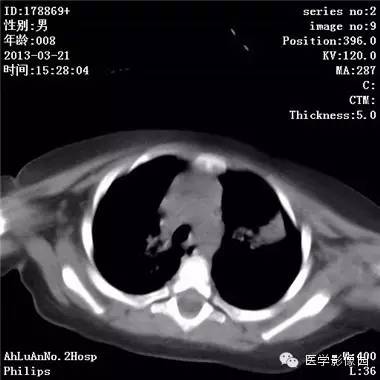

【病例】支气管异物1例CT影像表现

患儿男,8个月,呛咳,发热一周。实验室检查白细胞及中性粒细胞增高。

两肺肺纹理增多、增粗,右肺可见斑片状、片絮状模糊影,边界欠清;左肺上叶见楔形高密度影,内可见支气管征,尖端指向肺门;左肺下叶肺野透亮度增强;另见左肺主支气管内可见块状软组织密度影。

支气管异物(花生米)伴两肺炎症(追问病史,患儿奶奶层于一周前喂食患儿花生米,当时疑似“呛进去”,后来见好了也就没留意)。